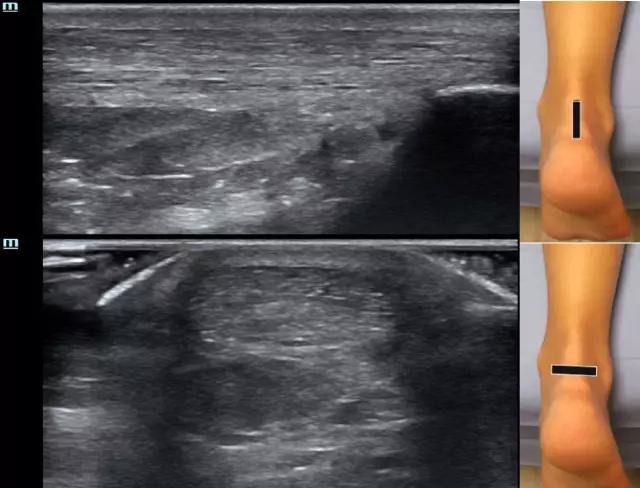

检查时,患者俯卧,足部垫高或悬于床外,从近端的肌-腱移行处开始扫查,直至末端跟骨附着处,扫查时注意长短轴结合,厚度一般在短轴时测量,约5-6mm。跟骨后滑囊正常可有少量积液,一般不超过3mm。

图2 正常跟腱长轴(上)及短轴(下)切面。